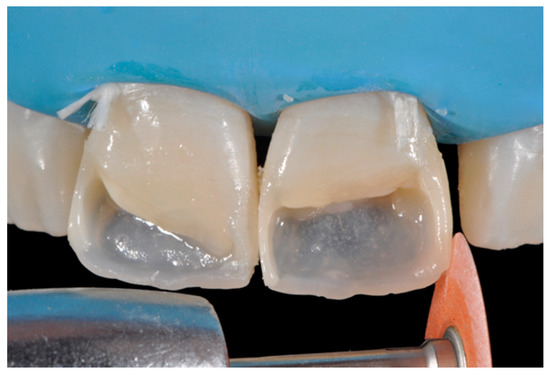

Once completed, the two frames (Clearfil Majesty ES-2, A1E, A2D, Kuraray Noritake Dental, Tokyo, Japan) showed internal and external excesses that were reduced using diamond burs and discs (Figure 33 and Figure 34) strictly following the procedure described in Section 2.1.2 of present article. Excesses were removed from the distal-incisal angle of #2.1 allowing therefore to obtain the desired translucency. After silane application and bonding procedure (Figure 35) as described in Section 2.1.2, restorations were completed (Figure 36 and Figure 37). They both show satisfactory clinical integration 1.5 years post-operative (Figure 38 and Figure 39).

Figure 33.

Frame imprecisions are corrected by reducing interproximal wall from the internal side. Reprinted from Restauri diretti nei settori anteriori, G. Paolone, S. Scolavino, © 2021, with permission from Quintessence Publishing Italy.

Figure 34.

Frame is also trimmed reducing external outline. Reprinted from Restauri diretti nei settori anteriori, G. Paolone, S. Scolavino, © 2021, with permission from Quintessence Publishing Italy.